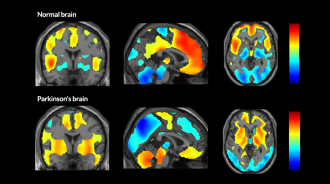

A brain at rest offers clues to Parkinson’s, Alzheimer’s

PET scans reveal that the breakdown of brain networks differs in Parkinson’s and Alzheimer’s diseases.